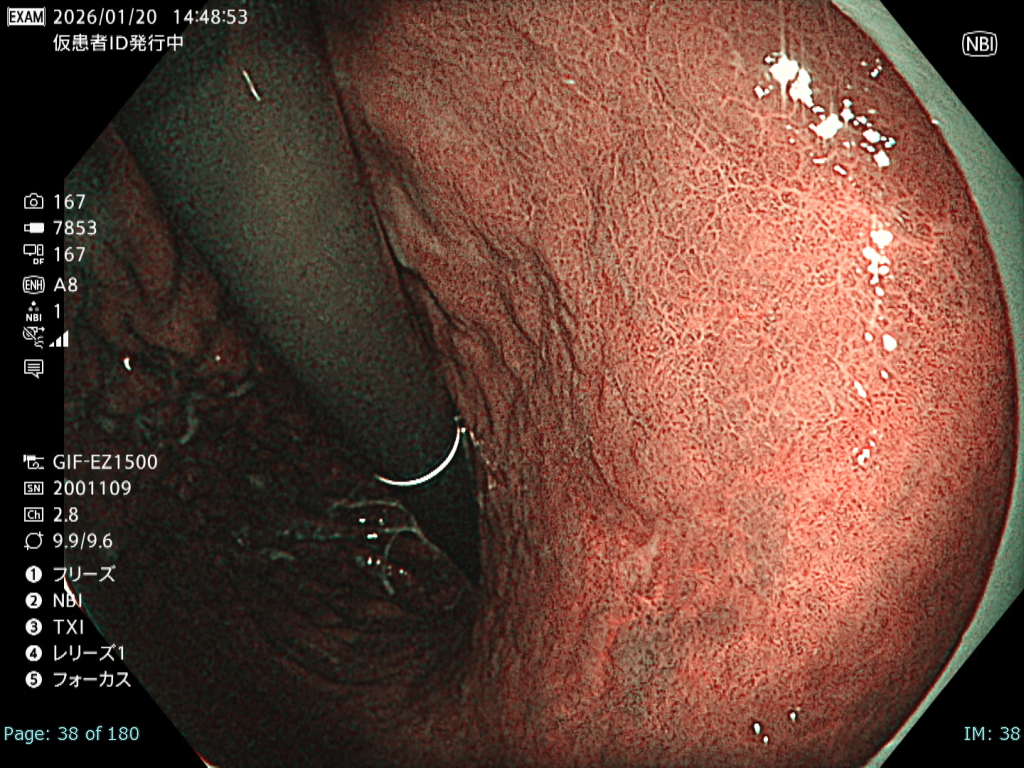

• NBI観察①(中遠景)

強調設定:B8

図3

観察中に出血が増加し、頻回の洗浄が必要となった。さらに胃管症例であったことから咳嗽が出現し、霧が生じるなど観察条件は不良であった。

• NBI+TXI観察① (中遠景)

切替前 NBI強調設定:B8

NBI+TXIレベル:中

図4

前述のとおり厳しい状況下でも、NBI+TXI観察モードは、NBI観察と比較して病変をよりシャープに描出出来ると感じた。